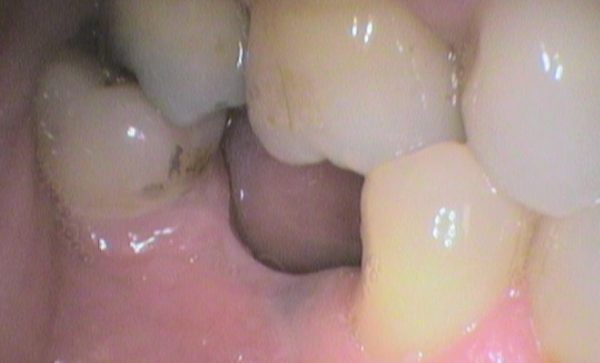

Case 32